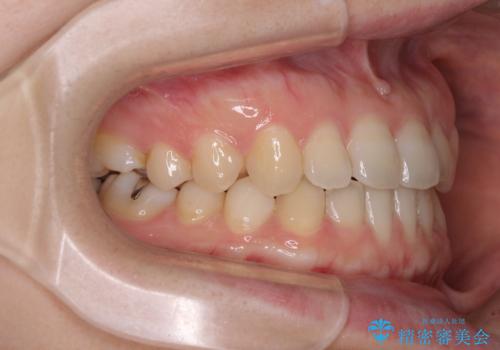

前歯のクロスバイト インビザラインによる矯正治療

- 前歯のクロスバイトとデコボコを気にして来院された患者様です。

骨格的に下顎前突傾向であるため、自己管理が煩わしくないようであれば、インビザラインによる矯正治療がお勧めとなります。

インビザラインを用い、下顎歯列を後方に移動させながら全市の被蓋を改善し、歯並びを整えていくこととしました。

途中マウスピースが使用できず、来院されない期間があり、治療期間は長くかかりましたが、無事に治療を終えることができました。